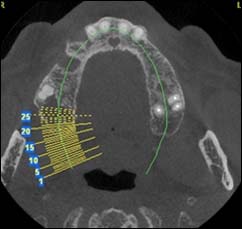

Examens tomographies volumiques type Scanner ou Cône beam

Dernière technologie à notre disposition, cette technique permet de voir en 3 dimensions des images de votre bouche et de mettre en évidence des pathologies ou des anomalies que les autres techniques ne permettent pas d’objectiver.

Coupe axiale